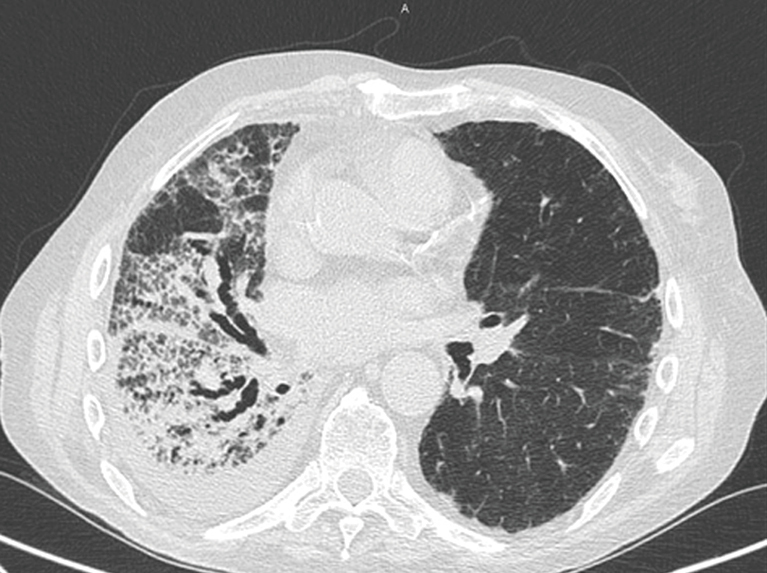

interstitial fibrosis pulmonary honeycombing end stage lung upper evident middle note field right

Interstitial Lung Disease, ILD, Usual Interstitial Lung Disease, UIP

lungs.thecommonvein.net uip interstitial lung lungs bronchiectasis ild diffuse heterogenous occasionally